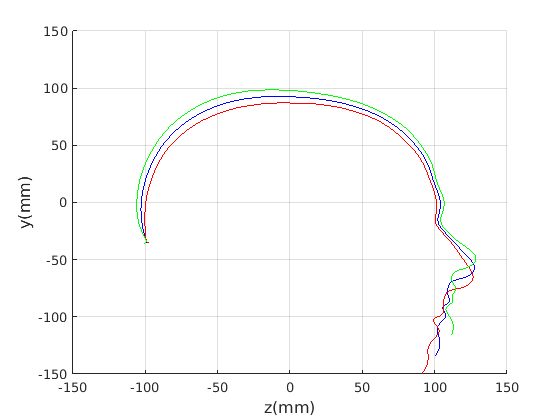

For the cranial sagittal profile model, when not scale-normalised (Fig. 20, left column), the following dominant shape modes are observed:

-

Cranial height variation with a low correlation with cranial length.

2.

-

A cranial bulge that varies between the front and rear of the cranium.

4.

When data is scale normalised (Fig. 20, right column), cranial height and length are more significantly correlated, as shown in the first mode (top right in figure). The second mode model a bulge that can vary from the front to the rear of the cranium. Taken together, these two modes capture close to 90% of the variation in the training set. A two-dimensional model, based on these two modes is used in a clinical case study in Sect. 8.

To provide a comparsion with ECN, the form/shape variation modes extracted from a GPA-based alignment are given in Fig. 21 for full head and Fig. 21 for cranium only.